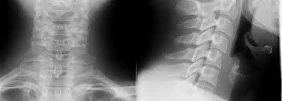

Vous effectuez une radiographie cervicale F+P sous minerve :